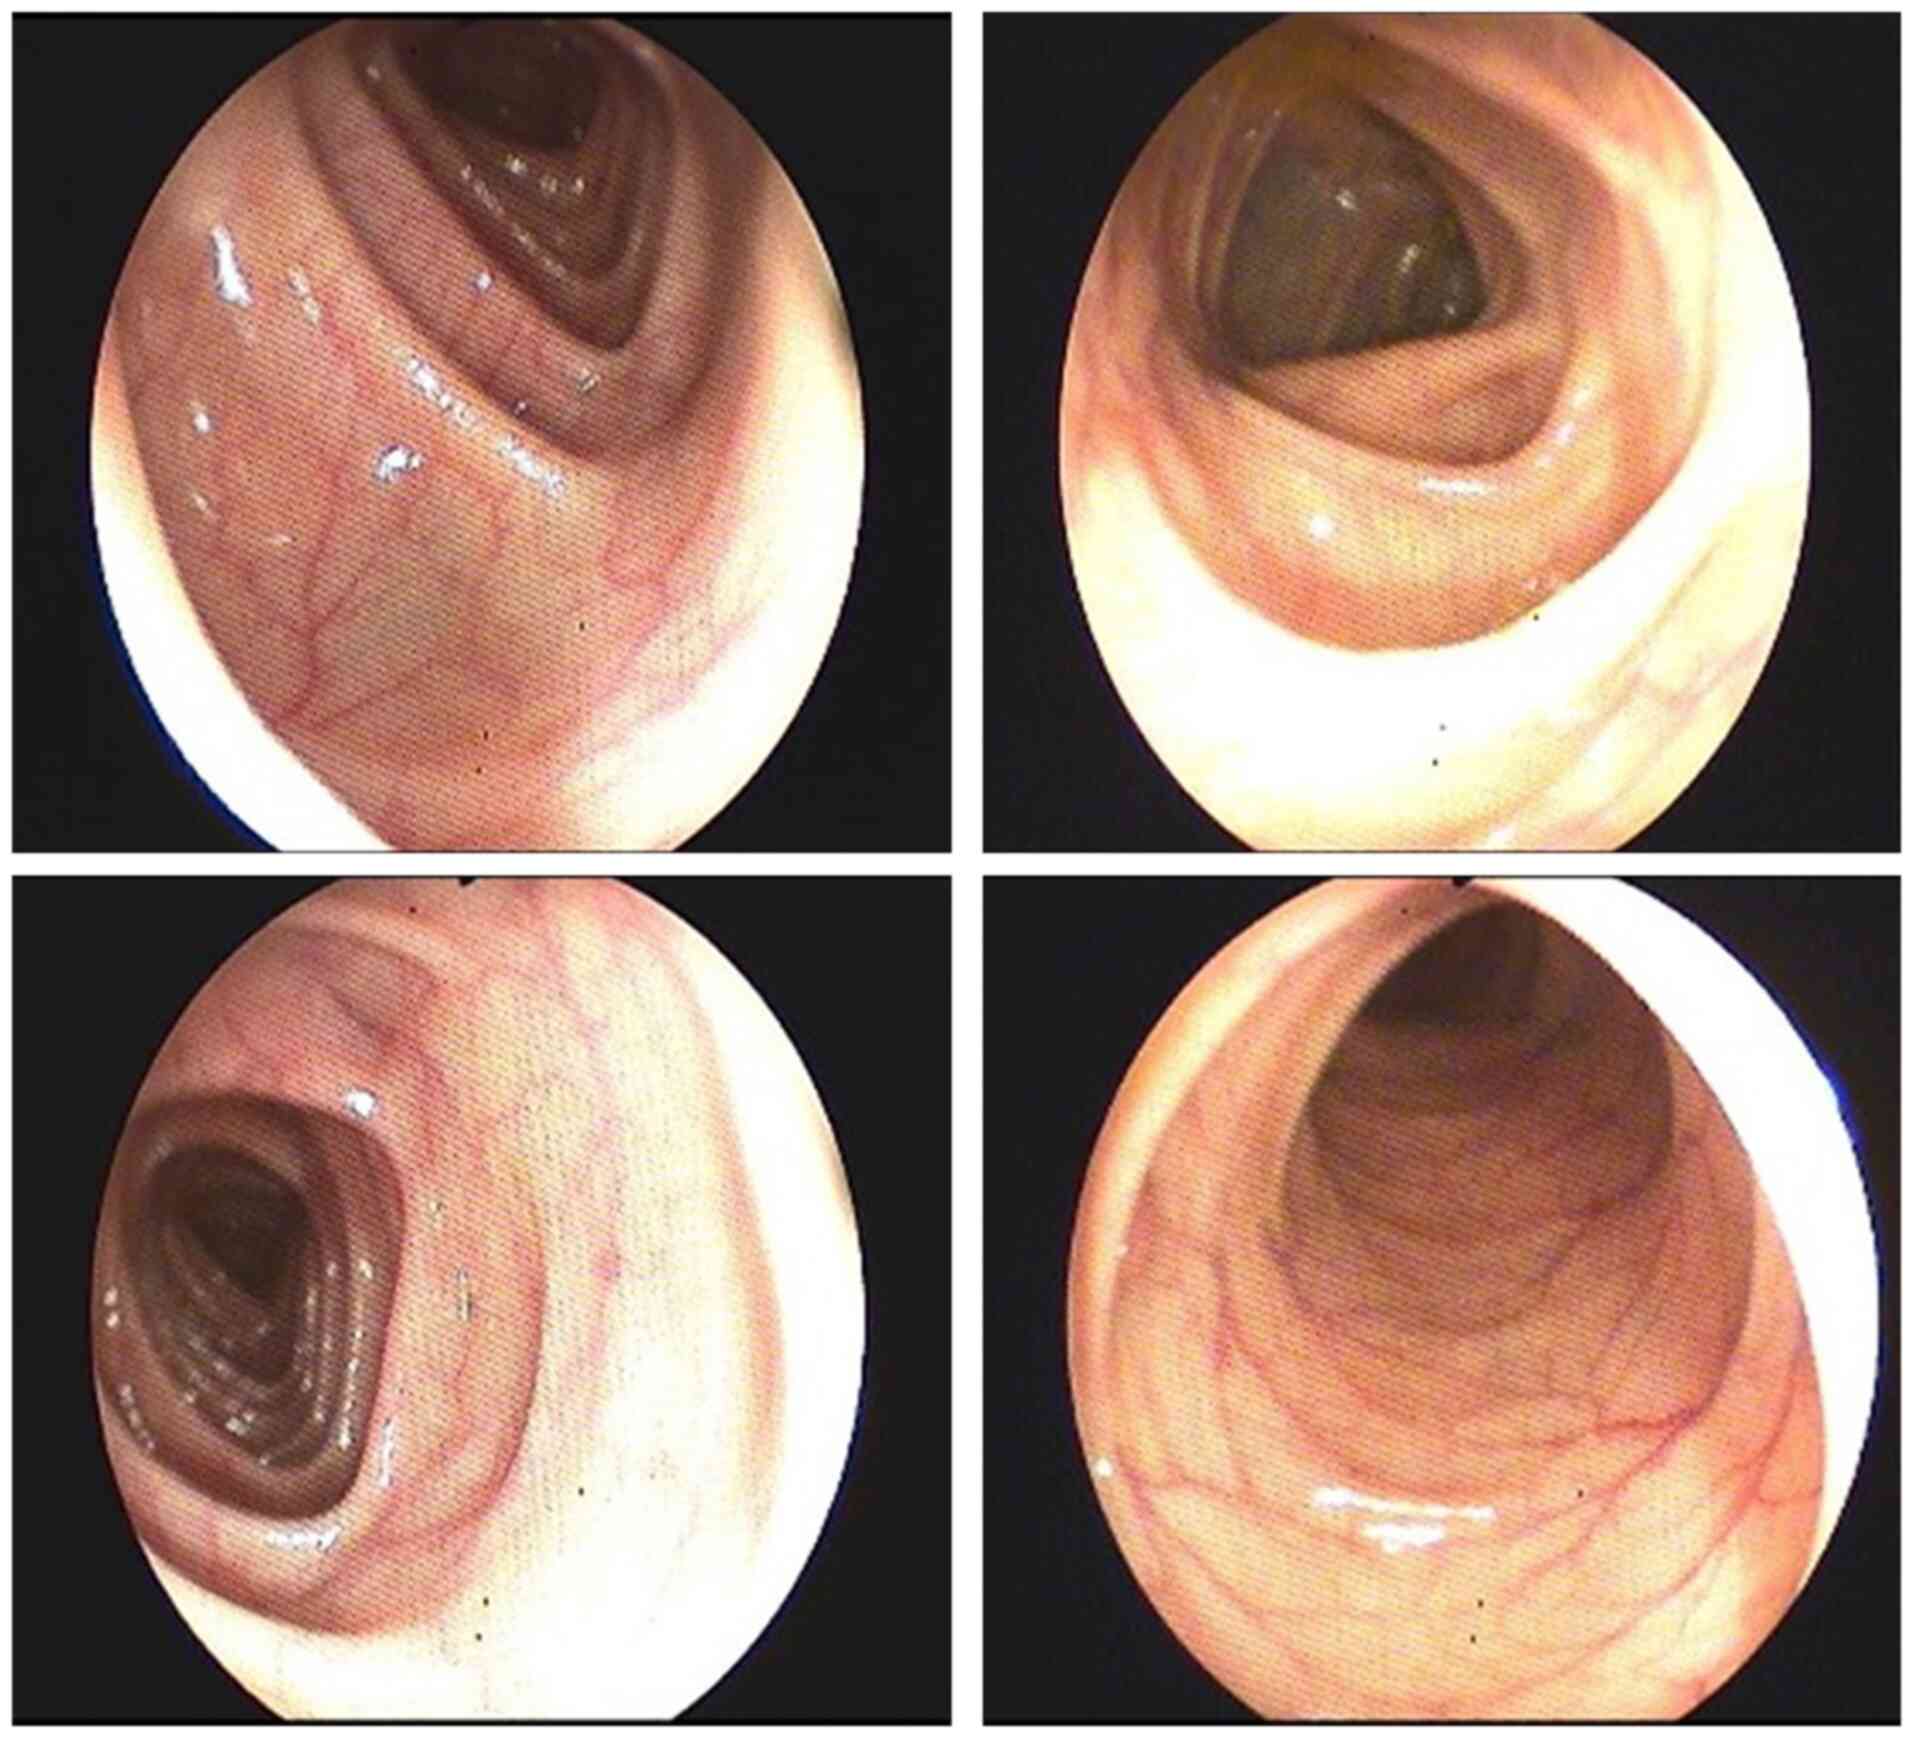

The blood work performed showed a hemoglobin of 11.1 g/dl confirming iron deficiency anemia, eosinophilia and negative tumor markers (carbohydrate antigen 19-9, α fetoprotein, carcinoembryonic antigen, cyfra 21-1). The abdominal ultrasound showed bilateral kidney stones. The chest X-ray revealed no pulmonary formations. Due to the fact that the patient had hypoanabolic syndrome and anemia, investigations continued with upper GI endoscopy which revealed gastroesophageal reflux (Fig. 2). Colonoscopy showed enlarged haustral folds (Fig. 3) and a few diverticular filling defects. There were no signs of tumors, inflammation or bleeding.

Figure 3

Colonoscopy. Enlarged haustral folds are evident.